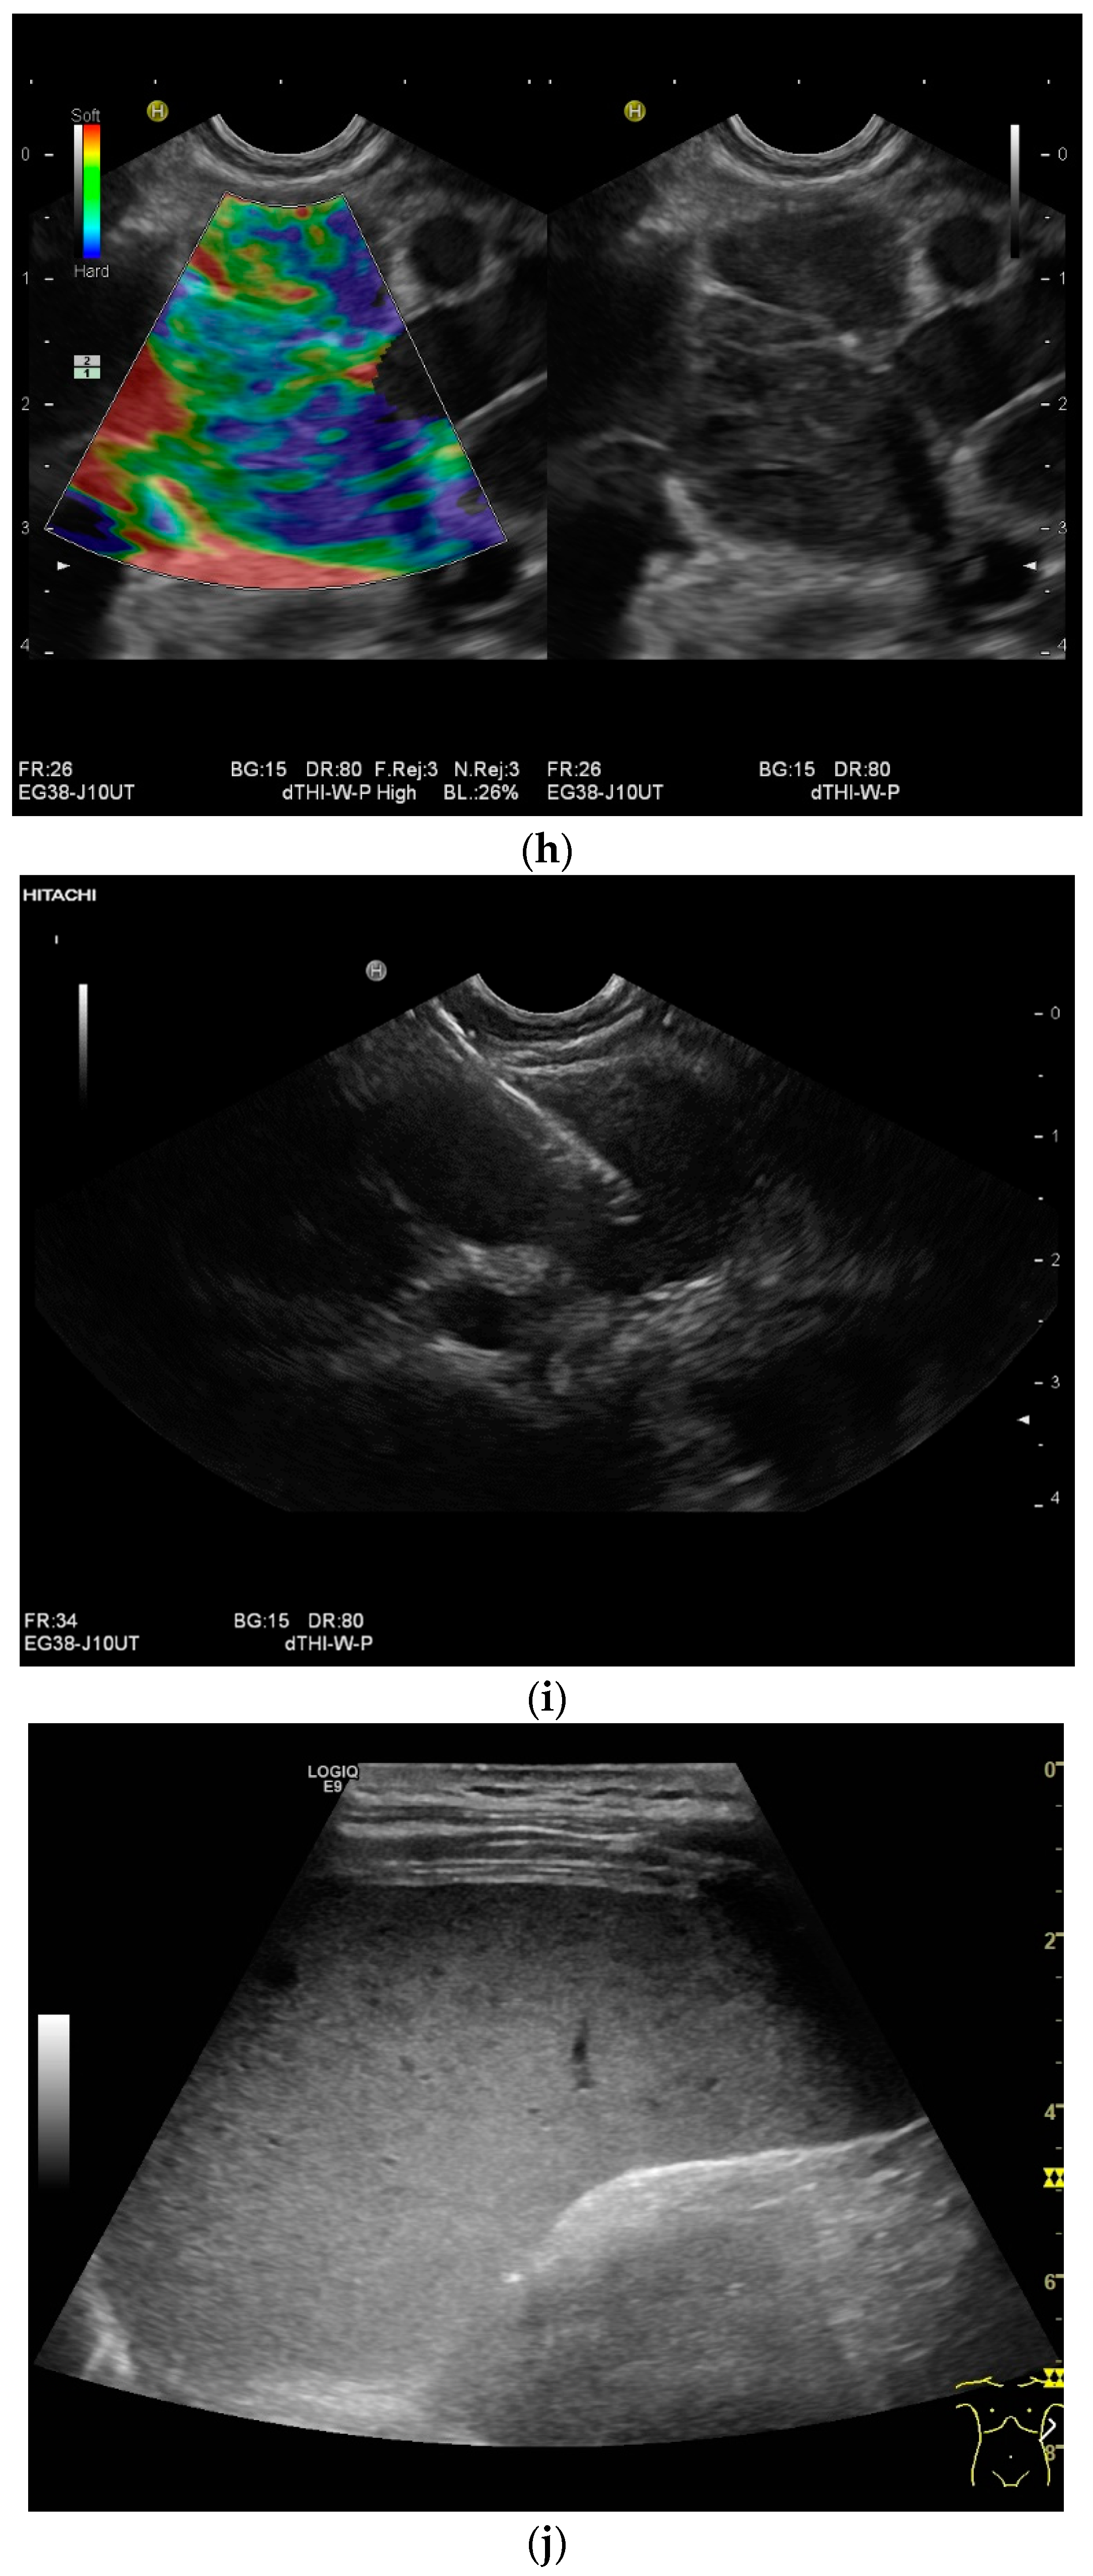

Spleen involvement usually only occurs in disseminated disease. The manifestations are splenomegaly, hypoechoic micronodular (miliary), or macronodular lesions [8,74], as well as splenic abscesses [75] [Figure 4a–d]. In a group of patients with tuberculosis and mostly advanced HIV infection, 37% had splenic lesions [5]. In 33%, splenic lesions were associated with lymphadenopathy, and 16% each had splenic lesions and ascites or splenic lesions, ascites, and lymphadenopathy. Micronodular lesions may be indistinguishable. If this is suspected, examination with a high-resolution linear transducer is recommended. Using CEUS, splenic lesions in the arterial phase showed a hyperenhancement, followed by either a slow washout or a persistent enhancement in the middle and late parenchymal phase [76]. A fast washout was the exception, but nevertheless was also possible. These exceptional cases would therefore be difficult to differentiate from malignancies. There was also rim-like enhancement with central nonenhancement, like abscesses and septation-like enhancement [76]. Another study using CEUS in splenic manifestations of tuberculosis presented homogeneous enhancement (6.7%), heterogeneous enhancement (63.3%), and nonenhancement (30.0%). Most of the cases showed low enhancement. Among these cases, heterogeneous enhancement was divided into septal enhancement type (21.1%) and marginal enhancement type (78.9%) [77] [Figure 4c–g]. The most important differential diagnoses are non-Hodgkin’s lymphoma and other granulomatous inflammations, such as sarcoidosis, especially in the presence of lymphadenopathy. The splenic lesions must be differentiated from mycotic abscesses, leukemic infiltrates, and metastases. In the meta-analysis conducted by van Hoving et al. [78], splenic lesions as manifestations of abdominal tuberculosis had a broad sensitivity of 13–62% in five studies using B-mode ultrasonography. The specificity was higher, at 86–100%.

Figure 4.

Sonographic and CEUS features of splenic tuberculosis. Sonographic and CEUS features of splenic tuberculosis. Subcapsular splenic lesion (arrow) (a), subcapsular splenic lesion using a linear transducer of 12 MHz (arrows) (b). Histologically confirmed tuberculosis from mediastinal lymph nodes. Multiple small splenic lesions (c). Using CEUS with a linear transducer (9 MHz), these are slightly hypoenhanced in the arterial phase (d), and show a progressive washout in the course of the venous phase (arrows) (e). Subcapsular splenic lesion (arrow) with nonenhanced and hypoenhanced parts and hyperenhanced rims indicate a caseous necrosis (f). In another section, an interrupted spleen capsule (arrow) due to a rupture of the caseous necrosis can be assumed (g).